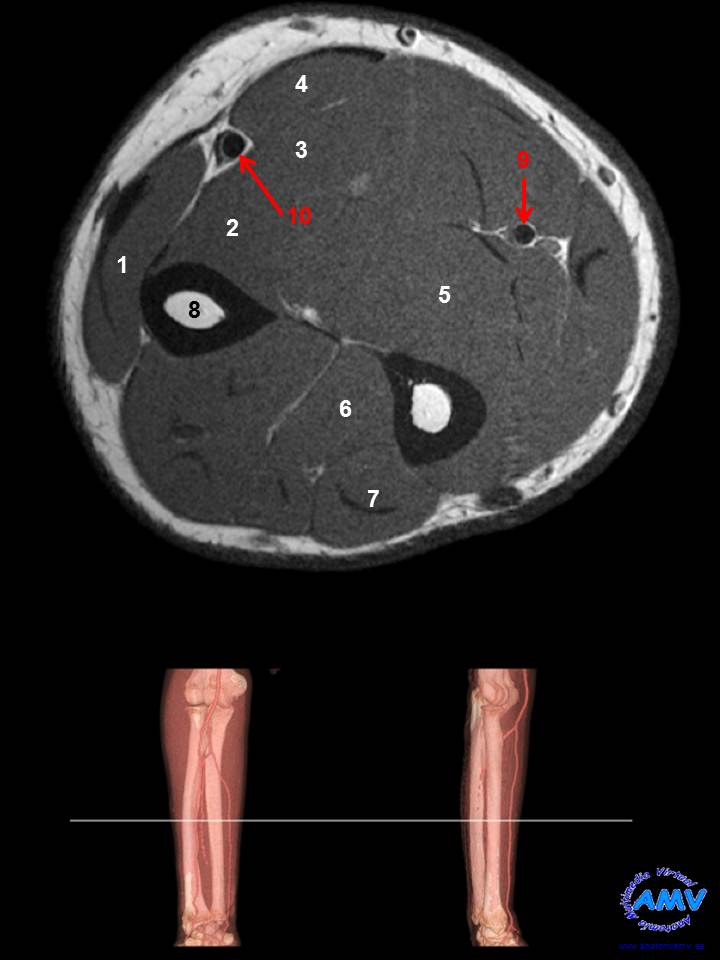

RMN Axial de Antebrazo

ms_rmn_08.jpgIndique que estructura se señala con el número correspondiente:

El nº 1 señala al músculo .

El nº 2 señala al músculo .

El nº 3 señala al músculo .

El nº 4 señala al músculo .

El nº 5 señala al músculo .

El nº 6 señala al músculo .

El nº 7 señala al músculo .

El nº 8 señala al hueso .

El nº 9 señala a la arteria .

El nº 10 señala a la arteria .